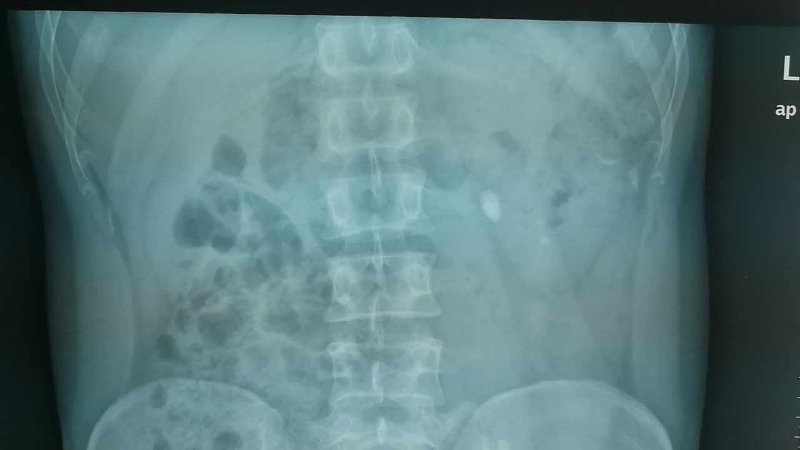

患者刘鹏 一例左输尿上段结石伴左多发小结石患者,体外碎石效果不佳,给予经皮肾镜碎石取石,手术总耗时约30分钟,术后未予留置肾造瘘管(无管化),一次清除结石。

术后三天患者即出院,大大缩短住院时间,患者痛苦更少。